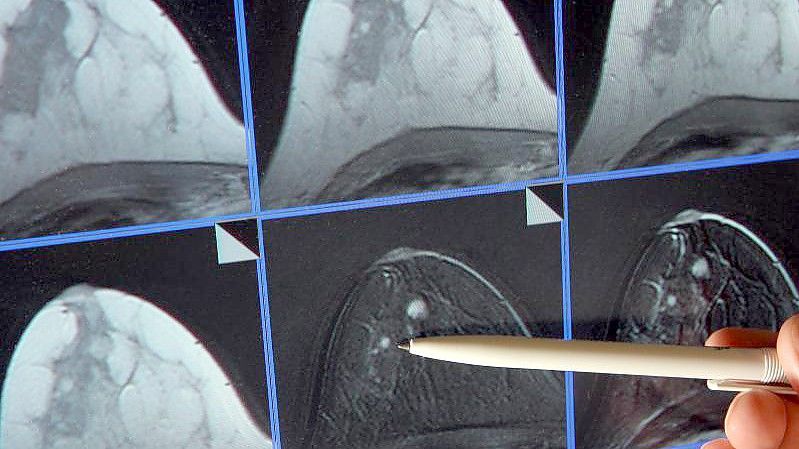

Das Bundesinstitut für Arzneimittel und Medizinprodukte hat Maßnahmen gegen einen Versorgungsengpass bei dem wichtigen Wirkstoff gegen Brustkrebs auf den Weg gebracht. Foto: Jan-Peter Kasper/dpa-Zentralbild/dpa